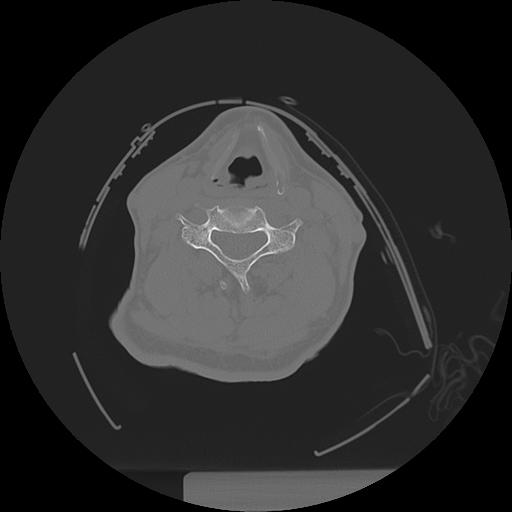

11 HUESO,,Axial,2.0,HUESO,,